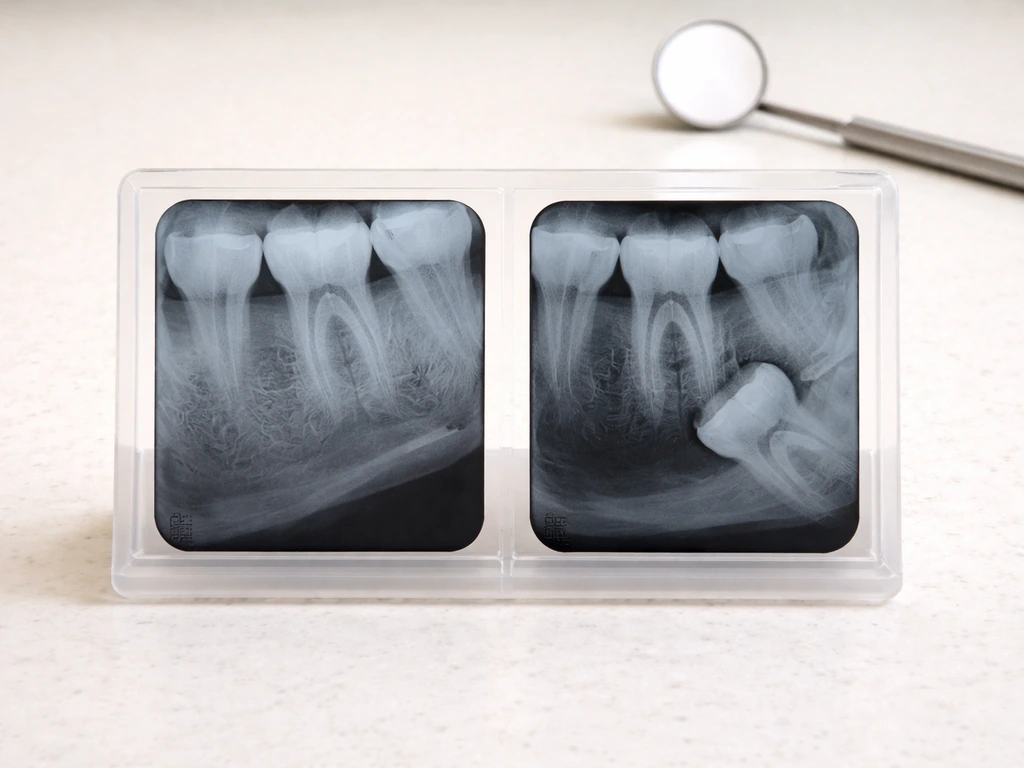

- Impaction on one side: A tooth blocked by bone, soft tissue, or an adjacent molar can get stuck while the other side erupts freely. The most common angulation patterns seen on X-rays are vertical (53%), mesioangular (22%), horizontal (20%), and distoangular (4%), and each affects how the tooth moves (or doesn't).

- Congenitally missing teeth: Some people simply don't develop all four wisdom teeth. Dental agenesis (a missing tooth bud entirely) is not rare, and without a panoramic X-ray, you'd never know.

Upper wisdom teeth often erupt more quietly. They tend to have a more forgiving angulation and slightly more space, so they can come through without causing the kind of dramatic jaw pain or swelling that makes you call a dentist. This asymmetry in symptom intensity can make it seem like you only have wisdom teeth on the bottom, or only on one side. If you're not sure which teeth you actually have, a panoramic X-ray will map all four corners at once and immediately answer the question.

For a left-versus-right check, don't rely on symptoms alone. Impacted teeth can sit silently in the jaw for years before causing trouble. Serial panoramic X-rays are actually studied specifically for their ability to predict whether a lower wisdom tooth will erupt on its own or stay impacted, which tells you that clinical observation alone isn't enough to know what's happening on the quieter side.

If symptoms are mild or you're simply curious about what's happening on both sides, book a routine dental appointment and ask specifically for a panoramic X-ray (OPG). A panoramic radiograph is the standard first-line imaging for wisdom tooth evaluation. It shows all four wisdom teeth at once, their angulation, their relationship to adjacent teeth and nerves (particularly the inferior alveolar nerve in the lower jaw), and whether any are impacted. The American Association of Oral and Maxillofacial Surgeons (AAOMS) recognizes the panoramic radiograph as the most commonly accepted imaging for third molar management. In situations where a lower wisdom tooth appears close to the inferior alveolar nerve canal, your dentist or oral surgeon may also recommend a CBCT (3D scan) to better assess the risk before any procedure.